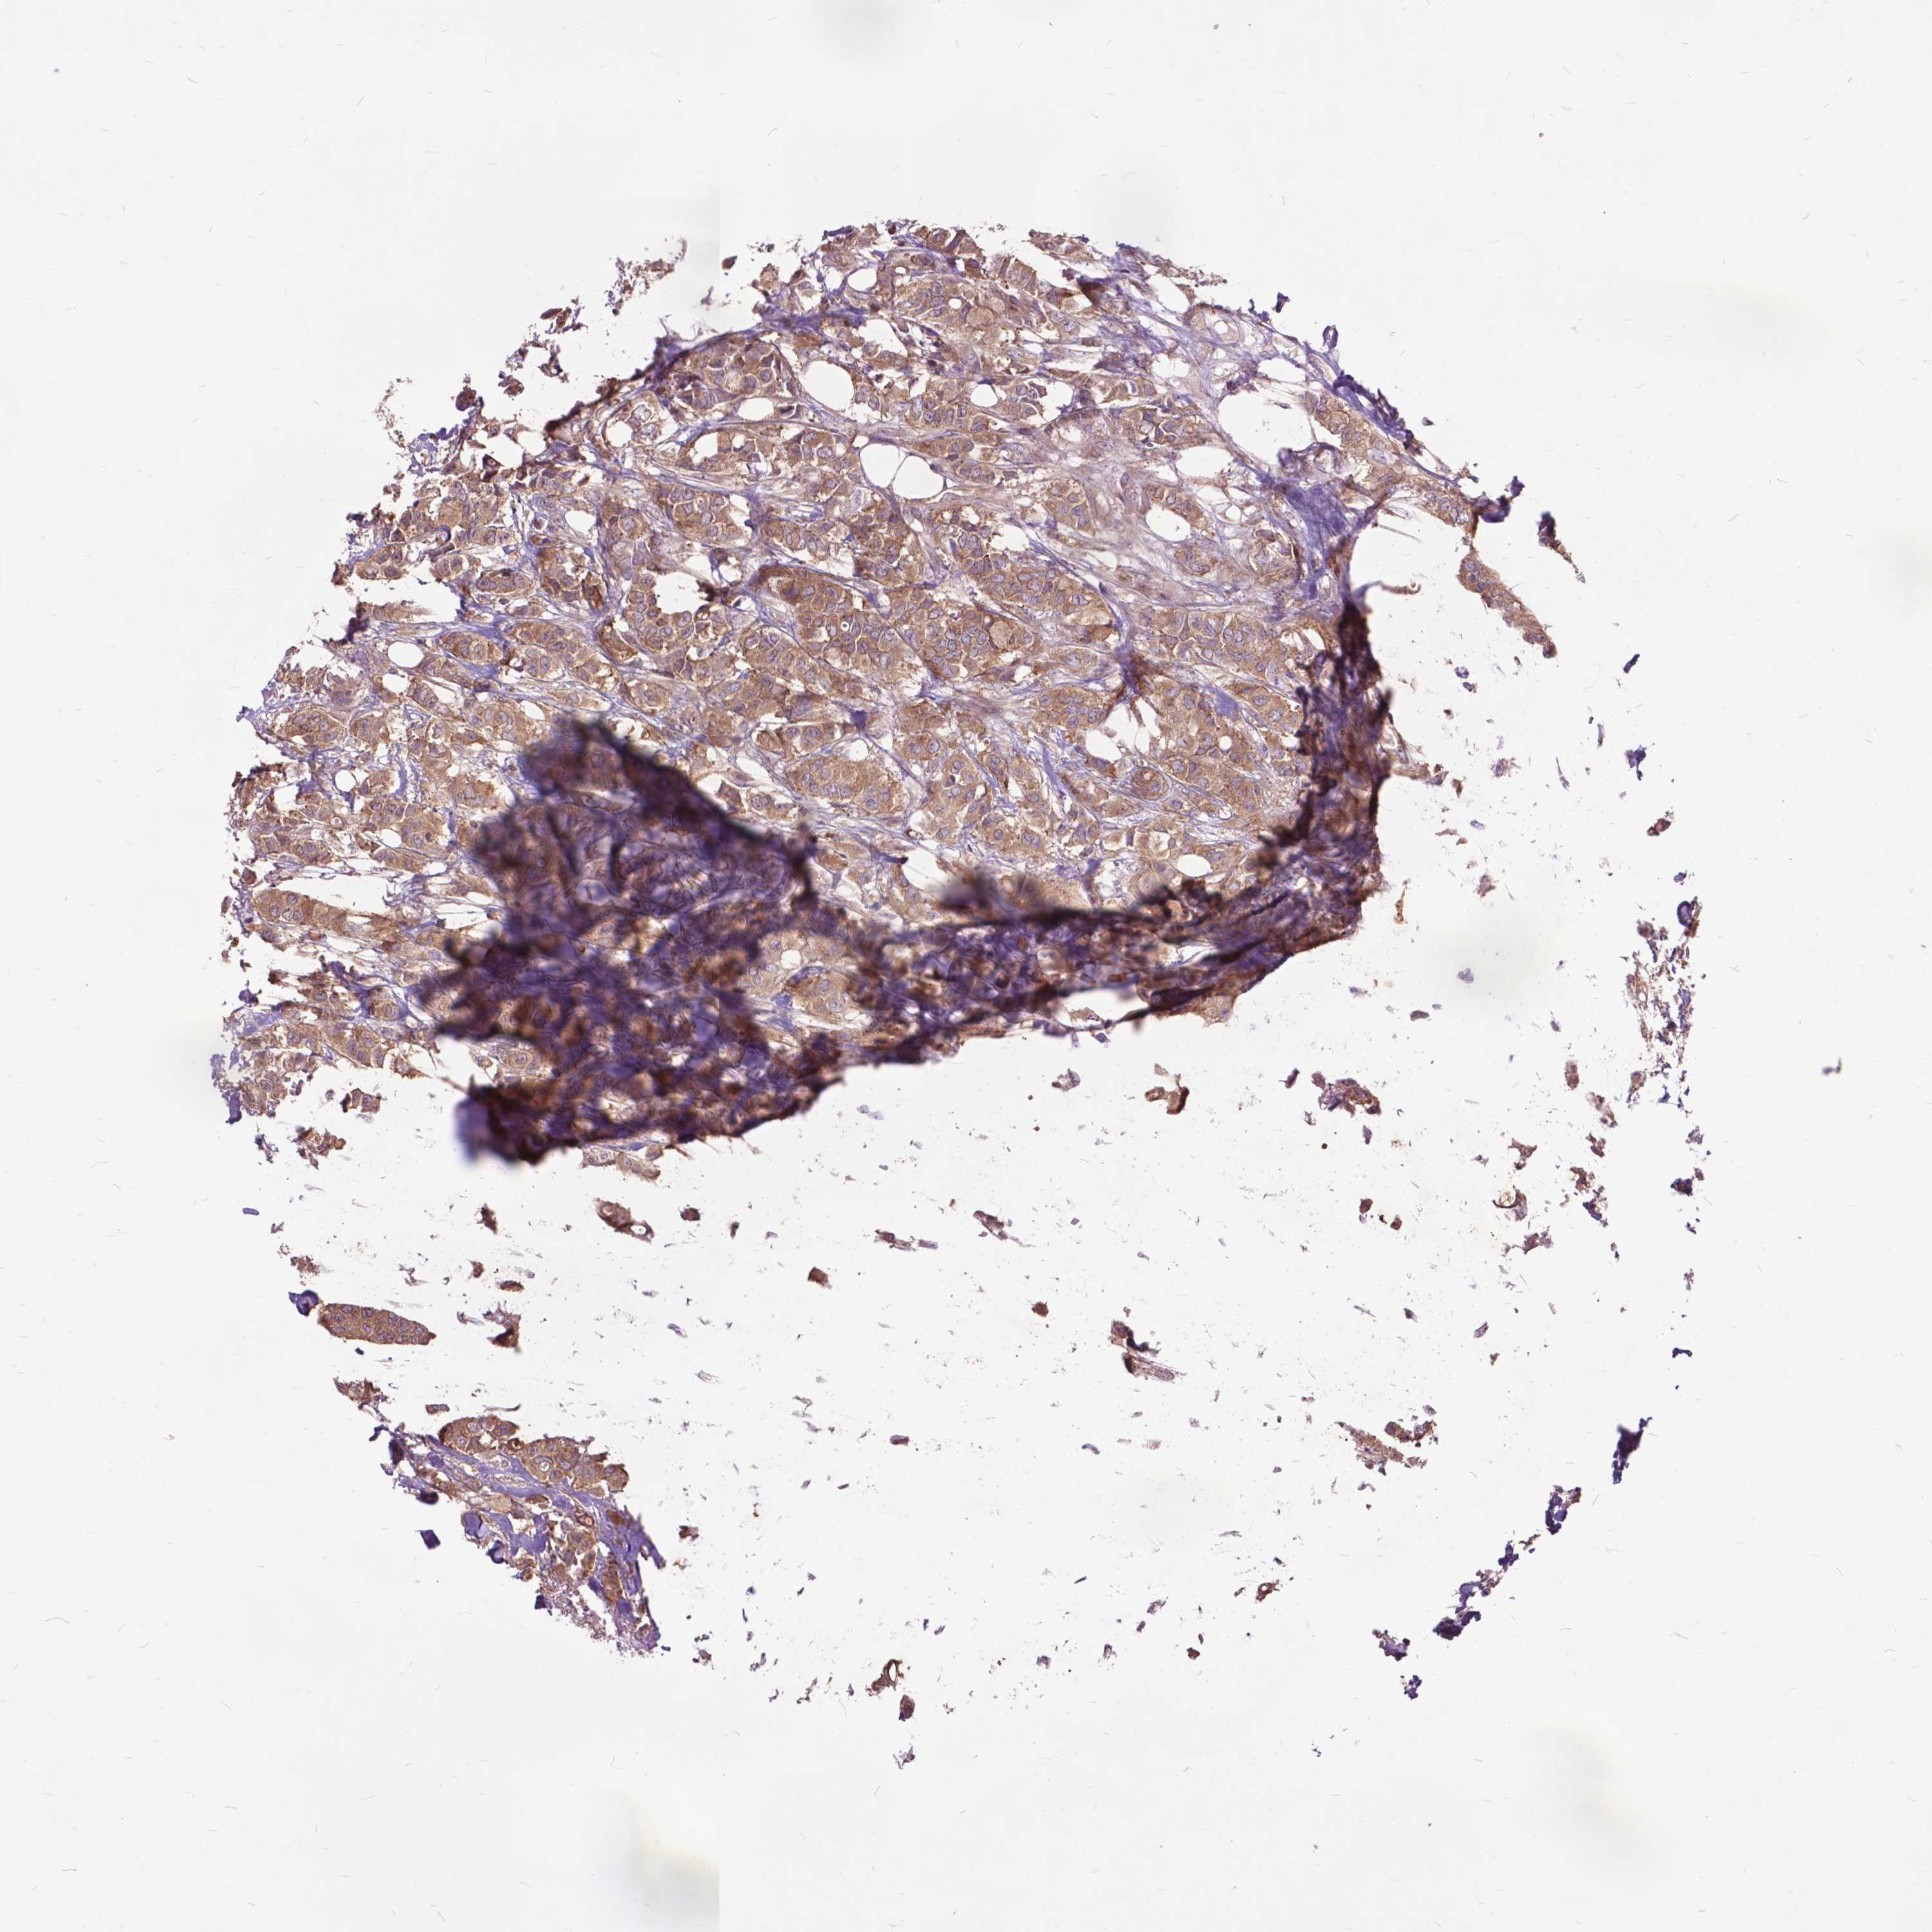

BRCA TCGA BRCA VALIDATION PROTEIN EXPRESSION

ANTIBODIES

AND

VALIDATION